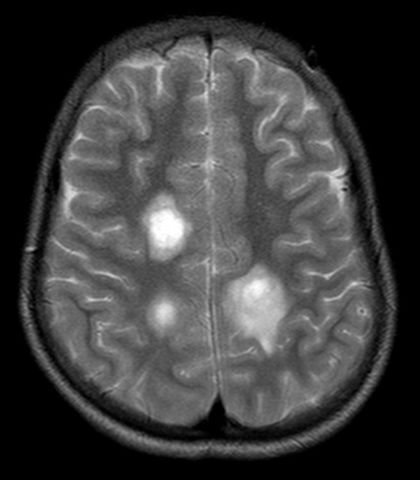

• Paul Broca

Paul Broca

Descubrió el centro del habla en el cerebro (área Broca o tercera circunvolución frontal izquierda) e hizo un mapeo de este.